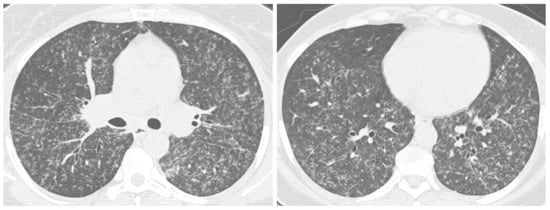

2.4. Disseminated Infection

2.5. Mixed Pattern